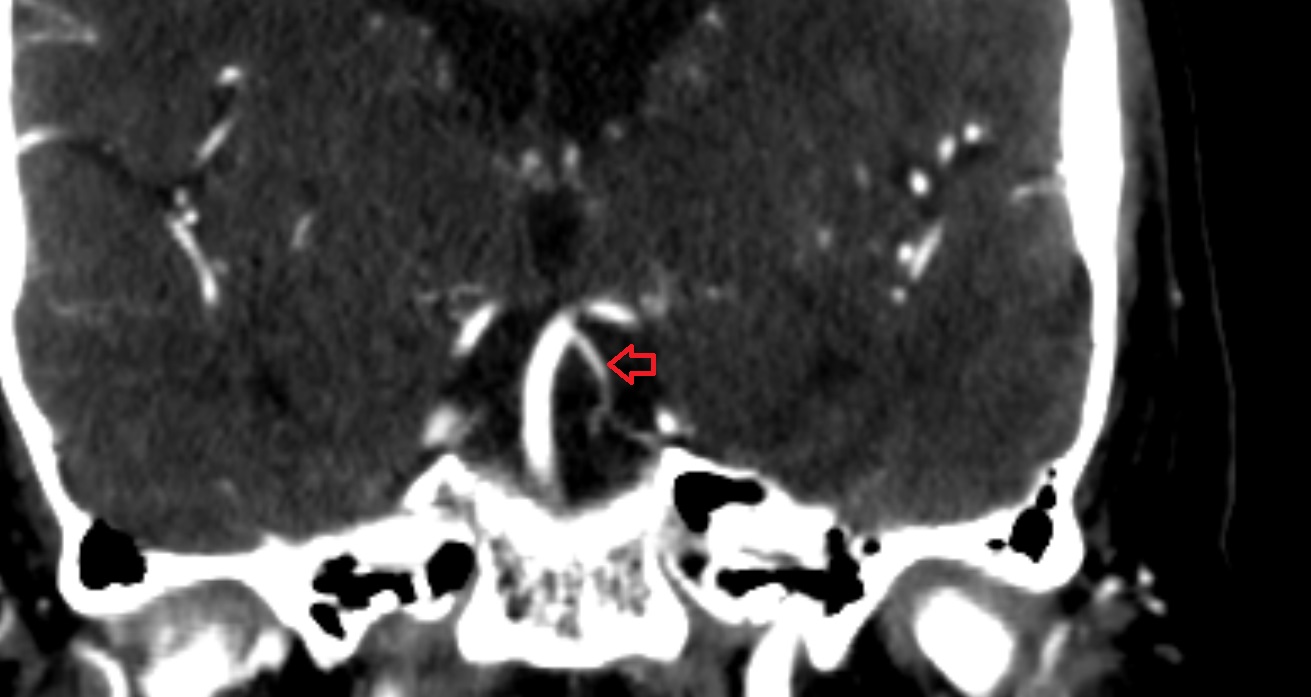

- Middle cerebral artery

- Middle cerebral artery horizontal segment (M1)

- Middle cerebral artery insular segment (M2)

- Middle cerebral artery opercular segment (M3)

- Middle cerebral artery cortical segment (M4)